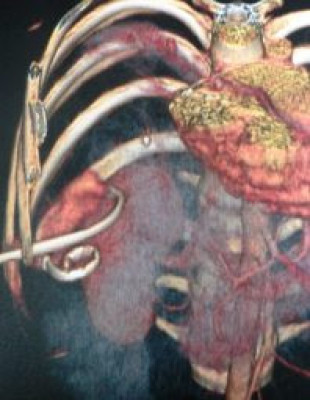

Drenaje percutáneo de absceso hepático

Envíado por Dr. Carlos Miguel Zavaleta Consuegra